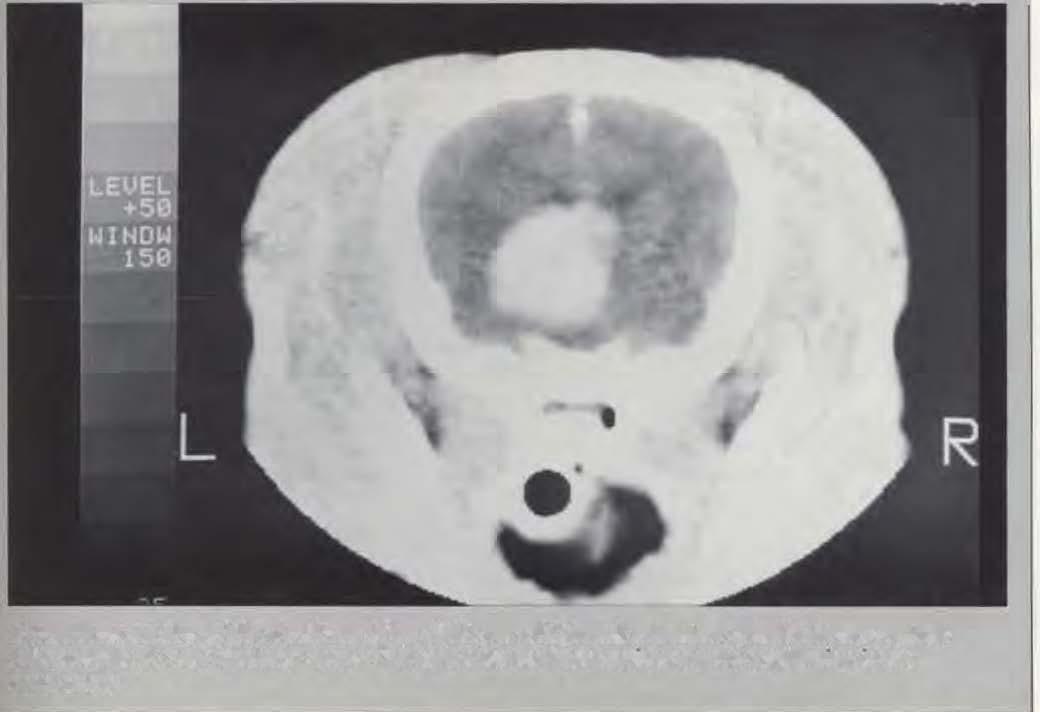

"CATScanandMagneticResonanceImaging."

Dr.Jeffrey A. Wortman discussed the new diagnostic tools available to radiologists atthe School. While radiographystill playsan important role. newtechnologysuchas nuclear mediune(sl...liltJgraphy), ulttCl.)Onography,�-rayLOmputed tomography(CAT Scan. X-cn.and magnetic resonance imaging(MRI) permit diagnosis ofdisordersthat may not bedetectable through radiography.

X-ra) computed tomography (CAT-Scan) is a sophisticated diagnostic tool the School ha.� access to at tht: Medical School radiology research facilities. A cross-sectional image is reconstructed from computer analysis of the transmitted x-ray data recorded by �ensitive detectors. The result is a detailed study ofanatomic pathologySoftwareprogramc; altnw the view of a body area in an operator-selected plane of interest, magnification: and measurements suc:h ali length. area. and \olume. X-CT is a powerful but expensive diagnostic tool. Here at the School it has been used primaril� to detect brain lesions. h has been Invaluable in detecting the precise location of these lesions. This is particularly important in cases involving brain tumors so that biopsy and or surgical removal may now be feasible. Animals have to be anesthetized for the CAT scan procedure.

A rransverse section ojthe cerebrum ofan eighT year oldfemale miniowrepoodleshows comras1 enhancemem cifa left thalamic moss. Thi� was o wmvr (hemangw.�orc·omo) originarmx m the mualca\'ill'.